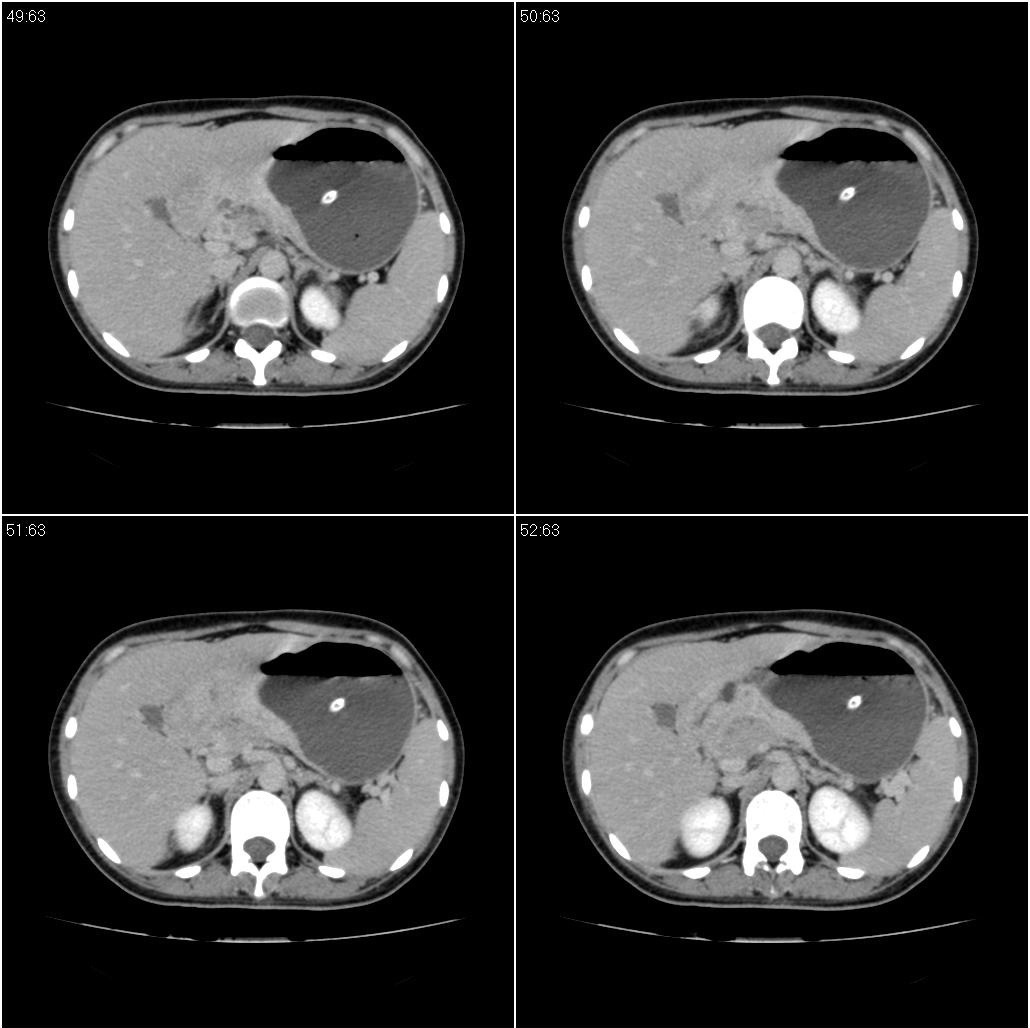

标题: CT21386:女性,33岁。4个月前因妊娠发现盆腔肿物。 [打印本页]

女性,33岁。4个月前因妊娠发现盆腔肿物。ca-125: 1100

胃幽门部癌伴小弯侧和腹腔淋巴结转移,胃内有胃管。

有明显淋巴结吗?我们感觉像是胰腺和胃窦。不过,胰腺尤其是胰头较大,不知道是否正常?

胃窦贲门胃小弯好像都厚啊 ,胃窦处比较明显,而且胃腔扩张明显,考虑胃癌伴梗阻。

胃壁局限性增厚,支持肿瘤性病变伴周围脓肿形成可能

未见明显肿大淋巴结,另肝脾大

高密度影是胃肠减压的管子。

支持;胃癌【浸润】幽门梗阻.胰头、胆囊及肝左叶受侵,副脾.